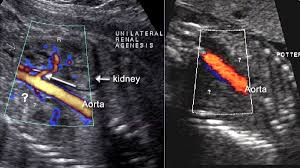

Doppler Ultrasound Of The Kidneys Ultrasound Vascular Ultrasound Ultrasound Sonography

It also allows to circumvent bowel gas and sometimes visualize the renal arteries better. The kidney wrongly senses the reduced flow as low blood pressure via the juxtaglomerular apparatus and releases a large amount of renin that converts angiotensinogen to angiotensin i. Kidney ultrasounds also called renal ultrasounds specifically target the kidneys and bladder.

The flank approach is practical for visualizing the mid and distal renal arteries more than the proximal renal artery. The central approach of renal transplant ultrasound is to evaluate for possibly treatable surgical or medical complications arising in the transplanted kidney. Any vessels identified must be traced to the kidney to confirm their identity. A renal artery doppler test is a type of ultrasound that measures the speed of blood flow in the arteries leading to the kidney explains webmd.